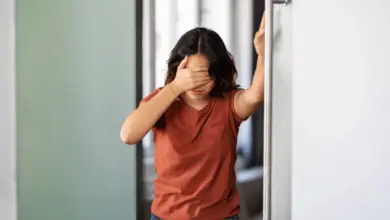

Problema na Coluna Dá Tontura?

Sim, problema na coluna dá tontura, principalmente quando a alteração está na região cervical, que é a parte do pescoço.…